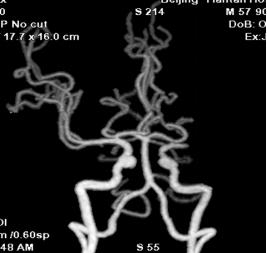

多模式CT影像提示:左侧大脑中动脉M1段闭塞,存在CBF-CBV不匹配。

术前影像

向右滑动查看更多

图2 CTA显示左侧大脑中动脉M1段闭塞

1.术前诊断:急性脑梗死,左侧大脑中动脉闭塞。

2.手术指征:患者应用阿替普酶溶栓后症状仍持续加重,CTA示左侧大脑中动脉闭塞。CTP存在CBF-CBV不匹配,有介入治疗指征。